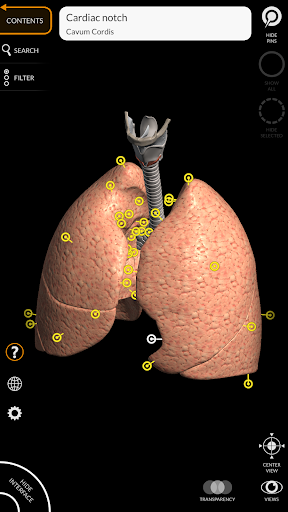

"Anatomía - Atlas 3D" permite estudiar la anatomía humana de forma fácil e interactiva.

A través de una interfaz sencilla e intuitiva es posible observar cada estructura anatómica desde cualquier ángulo.

Los modelos anatómicos 3D son especialmente detallados y con texturas de hasta una resolución de 4k.

La subdivisión por regiones y las vistas predefinidas facilitan la observación y el estudio de partes individuales o grupos de sistemas y las relaciones entre los diferentes órganos.

nervioso • Sistema respiratorio • Sistema digestivo • Sistema urogenital (masculino y femenino) • Sistema endocrino • Sistema linfático • Sistema ocular y auditivo CARACTERÍSTICAS • Interfaz sencilla e intuitiva • Rotar y hacer zoom en cada modelo en el espacio 3D • Opción para ocultar o aislar uno o varios modelos seleccionados • Filtro para ocultar o mostrar cada sistema • Función de búsqueda para encontrar fácilmente cada parte anatómica • Función de marcador para guardar vistas personalizadas • Rotación inteligente que mueve el centro de rotación automáticamente • Función de transparencia • Visualización de músculos a través de niveles de capas desde las superficiales hasta las más profundas • Al seleccionar un modelo o un pin, aparece el término anatómico relacionado • Descripción de los músculos: origen, inserción, inervación y acción • Mostrar/ocultar interfaz de usuario (muy útil con pantallas pequeñas) MULTILINGÜE • Los términos anatómicos y la interfaz de usuario están disponibles en 11 idiomas: latín, inglés, francés, alemán, italiano, portugués, turco, ruso, español, Chino, japonés y coreano • Los términos anatómicos se pueden mostrar en dos idiomas simultáneamente REQUISITOS DEL SISTEMA • Android 8.0 o posterior, dispositivos con al menos 3 GB de RAM Reversi

• Sistema respiratorio